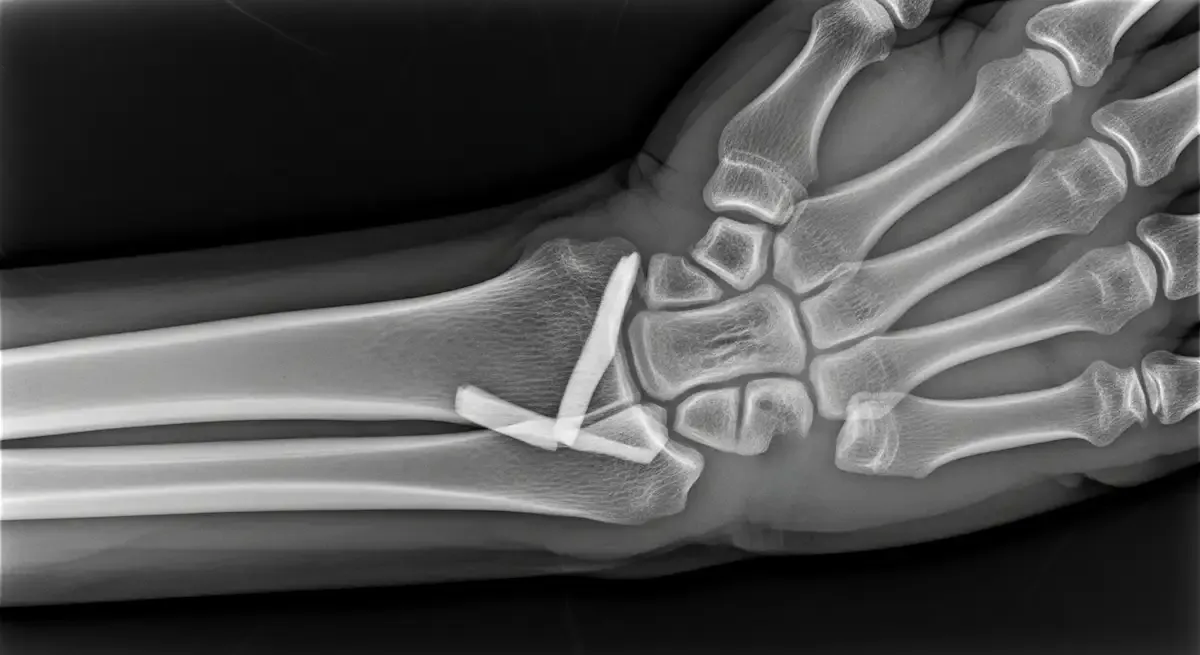

Como Saber Se Quebrei O Pulso? Sinais De Fratura

Após uma queda ou impacto direto na mão, surge uma dúvida comum no consultório: como saber se quebrei o pulso ou se foi apenas uma pancada? Essa diferenciação nem sempre é simples, já que fraturas, entorses e contusões podem causar sintomas...